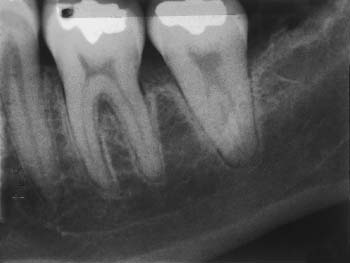

There is no convincing evidence that chronic periodontal disease is caused directly by occlusal overload. However, a widened periodontal ligament space (detected radiographically) may indicate premature occlusal contact and is often associated with tooth mobility (Fig. 4-24). Similarly, isolated or circumferential periodontal defects are often associated with occlusal trauma. In patients with advanced periodontal disease who have extensive bone loss, rapid tooth migration may occur with even minor occlusal discrepancies. Tooth movement may make it difficult for these patients to institute proper oral hygiene measures, and the result may be a recurrence of periodontal disease. Precise adjustment of the occlusion is probably more crucial in patients with a compromised crown/root ratio than in those with better periodontal support (see Chapter 32).